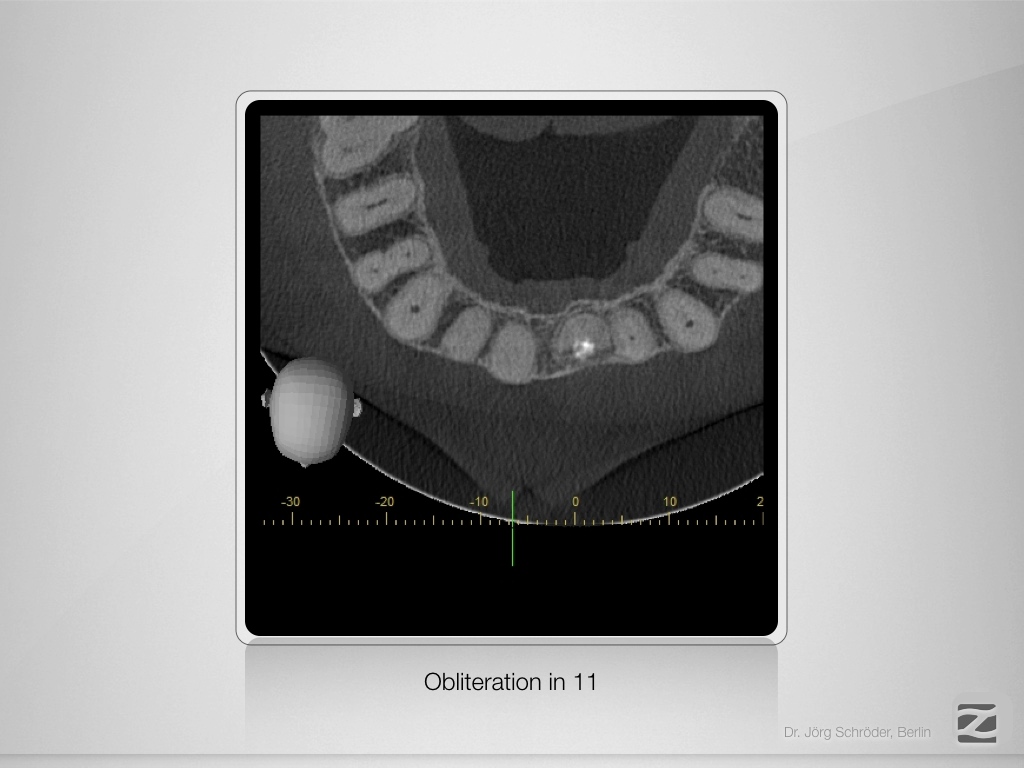

11D.010

„Guided“ geplant und „Guarded“ gemacht